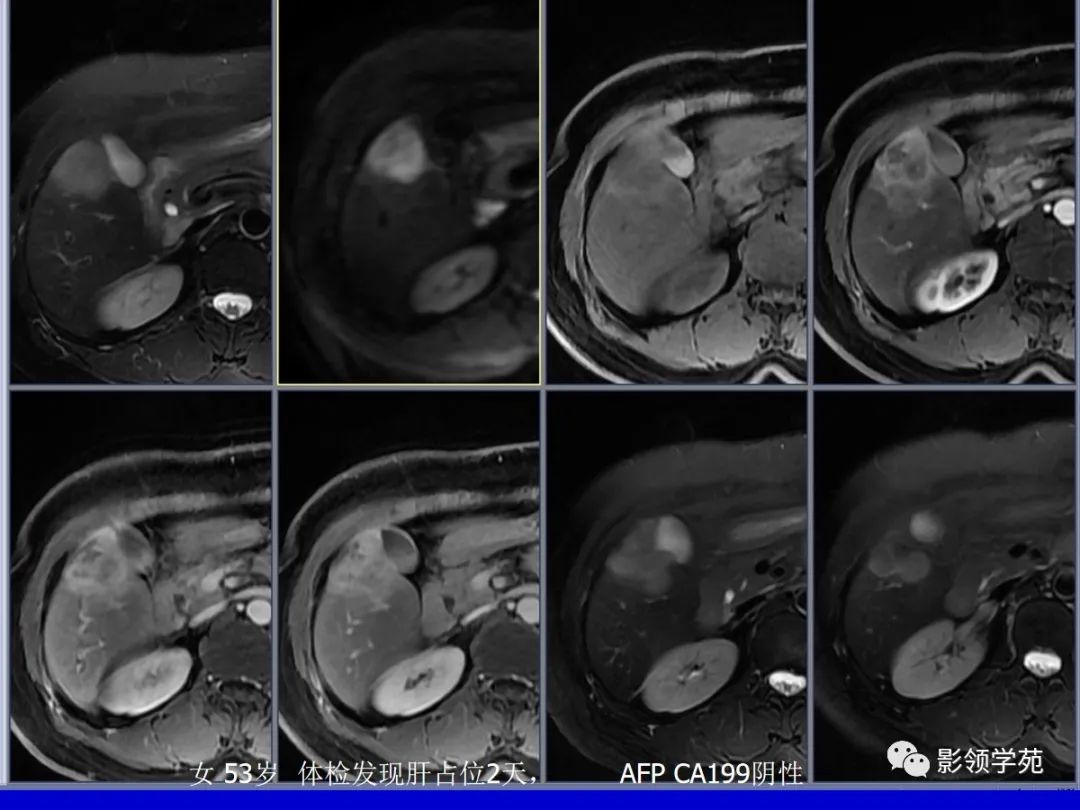

肝细胞肝癌(HCC)与胆管细胞癌(ICC)影像诊断要点